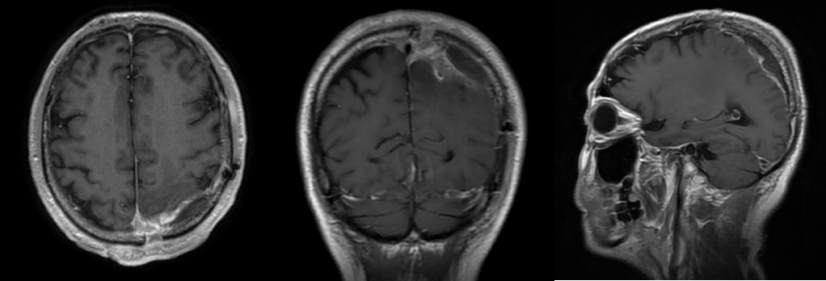

团队采用显微外科技术,沿肿瘤边界层层推进、毫米级剥离。从清晨到午后,历时8小时,最后一缕瘤体被完整取下,所有人悬着的心才稍稍放下。术中出血控制理想,重要静脉窦完好保留。术后病理回报:良性脑膜瘤(WHO 1级)。

在神经外科护理团队的精心照护下,苏先生恢复顺利。复查显示肿瘤完整切除,无出血、无感染。他的右侧肢体力量逐日恢复,未出现任何瘫痪或癫痫后遗症。出院时,他已能自如行走、抬手,生活重回正轨。